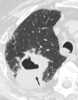

Cavitating pneumonia

Pneumonia is an inflammatory condition of the lung primarily affecting the small air sacs known as alveoli. Symptoms typically include some combination of productive or dry cough, chest pain, fever and difficulty breathing. [Source: Wikipedia ]